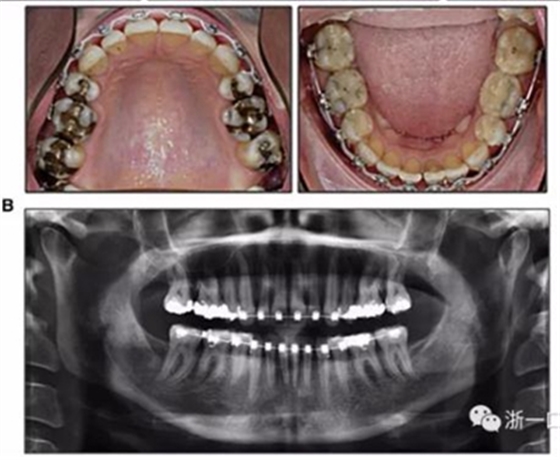

擴(kuò)弓保持8周后,除擴(kuò)弓器影響牙外粘接托槽,使用0.014鎳鈦絲進(jìn)行排齊、整平。旋轉(zhuǎn)停止后3個(gè)月拆除擴(kuò)弓器,全口粘接托槽,使用0.016niti繼續(xù)排齊整平。佩戴可摘保持器,保持上頜寬度。在使用至0.018x0.018niti7周,徹底排齊整平后,使用大弓型的0.016x0.022不銹鋼絲,繼續(xù)維持原有寬度,同時(shí)停止使用可摘保持器。掛II類(lèi)牽,糾正磨牙關(guān)系,使用鏈圈關(guān)閉散在間隙,少量使用IPR去除局部前牙的黑三角。術(shù)后9個(gè)月拍全景示,牙根平行度可,再無(wú)其他牙根出現(xiàn)問(wèn)題。1年7個(gè)月后治療結(jié)束。上下頜3-3舌側(cè)保持器+哈雷氏保持器進(jìn)行保持。

患者側(cè)貌改善,下唇唇肌緊張消失,上下唇可自然閉合。磨牙及尖牙關(guān)系糾正至I類(lèi),覆合覆蓋正常。上下頜弓型糾正至卵圓形,牙弓寬度增加。頭影測(cè)量分析示SNA角81.8°,ANB角3°。頭影測(cè)量重疊圖示下頜骨向后旋轉(zhuǎn),垂直面高度略有增加。

19個(gè)月后復(fù)查,情況穩(wěn)定,牙弓寬度穩(wěn)定。